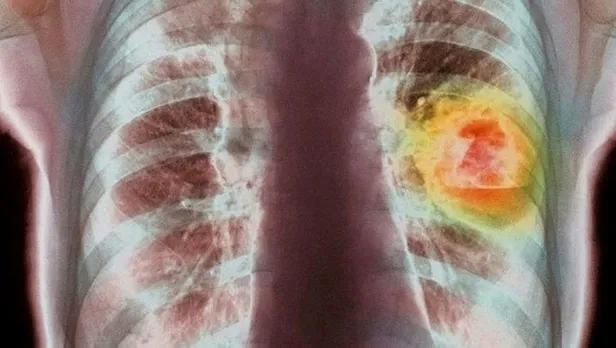

Kanser, günümüzde giderek yaygınlaşıyor. En sık görülen türü olan'akciğer kanseri' ise genellikle erkekleri tehdit ediyor. Çoğunlukla yaşam kaybına yol açan bu hastalıkla mücadelede, erken teşhis ve doğru tedavi önem taşıyor. Prof. Dr. Abdullah Erdoğan, bilinmesi gerekenleri TAKVİM için açıklıyor.

Akciğer kanseri, genellikle 40-50'li yaşlarda görülüyor. Kimi zaman daha erken yaşlarda ortaya çıkıyor. Korunmanın yolu, öncelikle sigaradan uzak durmaktan geçiyor. Kanserin, kan ve lenf yoluyla yayıldığını belirten Prof. Dr. Erdoğan,"Erken evrede akciğer kanser şikayeti bronş sisteminden başladığı için genellikle öksürüktür. Özellikle sigara içen, meslek hastalığına sahip olan, astımı ya da KOAH'ı olan kişiler geçmişte de öksürdüklerini düşünerek belirtiyi göz ardı eder. Ancak sigara içerken oluşan öksürükle akciğer kanserinin başlangıcında olan öksürüğü birbirinden ayırmak gerekir. Duyarlı bir hasta öksürüğünün şeklinin değiştiğini, eski öksürüğünden farklı bir forma girdiğini ayırt eder ve doktora başvurur. Kanserde tahriş olmaya bağlı olmayan, geceleri de süren karakteristik bir öksürük söz konusu" bilgisini veriyor.

Akciğer kanserinden korunmak için öncelikle sigara, tütün ve tütün ürünleri bırakılması öneriliyor. Basit bir akciğer filmi o hastalığın erken yakalanmasını sağlıyor. Bu nedenle 40 yaşından sonra yılda bir defa kontrol ve akciğer grafisi öneriliyor. Prof. Dr. Erdoğan,"Çok sigara içmek ile az sigara içmek arasında büyük bir fark yoktur. Az sigara içmek daha az zararlı olsa da kanser gelişimini başlatabilir. Çok içen kişiye göre risk oranı biraz daha düşüktür" diyor.

Akciğer kanseri, erken evrede fark edildiğinde cerrahi yöntemle tedavi edilebiliyor. Erken evrede yakalanamayan akciğer kanserlerinde kemoterapi ya da radyoterapi gibi diğer tedavi modeliteleriyle devam ediliyor. Cerrahide tümörü uzaklaştırmak ve hastaya konforlu bir yaşam sunmak amaçlanıyor. Cerrahide tümörün yayılma ihtimali olan lenf nodları da tümörle birlikte çıkarılıyor.